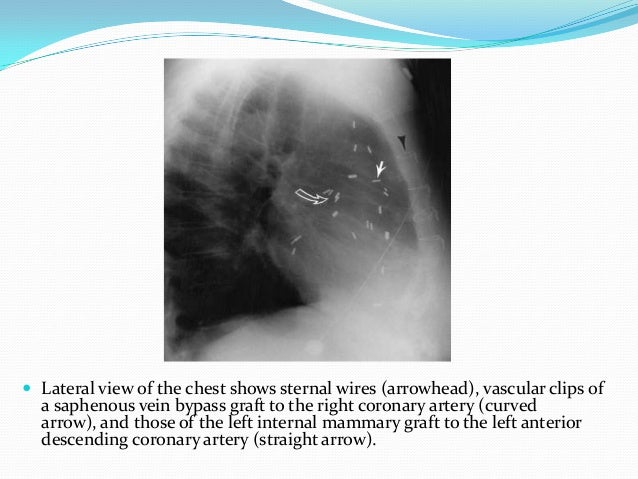

Chapter 3 Imaging Of The Heart And Great Vessels Radiology Key

radiologykey.com